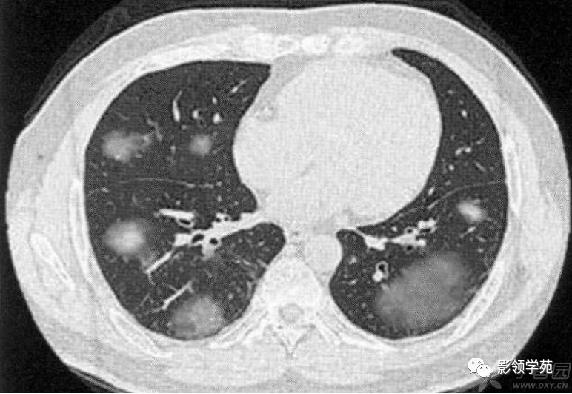

肺内多发结节和肿块是肺Wegener肉芽肿最常见的影像征象,表现为两肺散在分布、多发大小不等类圆形结节或肿块影,以两肺中下野分布多见。部分结节和肿块内可见空洞,洞壁多较厚,内缘光滑或不规则,空洞呈边缘性强化。合并感染时空洞内可形成液-气平面。结节或肿块周围一般都有较短毛刺,部分病灶有长毛刺与邻近的胸膜相连,表现为胸膜凹陷征。这与病理上结节周围存在大量成纤维细胞以及以纤维化形式愈合有关。

结节或肿块周围可见晕轮征、供养血管征。晕轮征提示肺结节或肿块出血,CT表现为结节或肿块周围磨玻璃密度影;供养血管征CT表现为血管影进入结节或肿块内,提示病变以血管为中心生长。

病例1:双肺多发大小不等结节,右肺中叶结节周围见晕轮征及供养血管征。

病例3:双肺多发结节伴空洞,部分空洞见气液平面。

病例4:左肺斑片状实变,右肺中下叶结节灶,中叶结节见供养血管征。